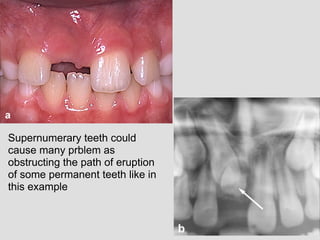

Supernumerary teeth could

cause many prblem as

obstructing the path of eruption

of some permanent teeth like in

this example

If impacted they could be asymptomatic